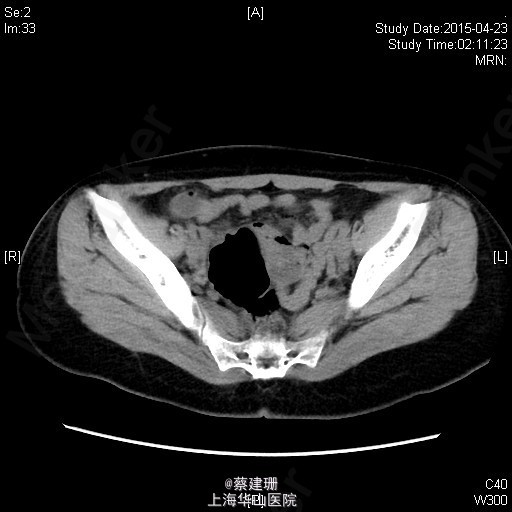

急性阑尾炎(粪石?)伴局限性腹膜炎

患者 女性 24岁,因“转移性右下腹痛一天余。”入院。患者一天前无明显诱因下出现中上腹疼痛,无恶心呕吐,无腹泻。10小时前疼痛转移至右下腹,原先中上腹疼痛缓解,无发热无腹泻。患者未予重视,后疼痛难忍于今日凌晨至我院急诊就诊,血常规示:WBC:18.63*10^9/L,我院B超示:右下腹见肠段局限性扩张,炎性病灶待排。肝胆胰脾肾未见明显异常,双输尿管未见扩张。我院CT示:阑尾增大壁增厚内见高密度影及低密度气体影,符合阑尾炎改变,盆腔少量积液。患者拒绝行急诊手术,故予以保守治疗,患者症状未缓解,右下腹疼痛加重。为行进一步诊治,收入院。

全身皮肤粘膜未见异常,无肝掌,全身浅表淋巴结无肿大。腹平坦,腹壁软,右下腹压痛,伴有肌紧张及反跳痛,麦氏点压痛(+),肝脾肋下未触及,肝肾脏无叩击痛,肠鸣音4次/分。 辅助检查:血常规示:WBC:18.63*10^9/L,N:89%。我院B超示:右下腹见肠段局限性扩张,炎性病灶待排。肝胆胰脾肾未见明显异常,双输尿管未见扩张。我院CT示:阑尾增大壁增厚内见高密度影及低密度气体影,符合阑尾炎改变,盆腔少量积液。

入院后诊断:急性阑尾炎伴局限性腹膜炎。完善相关检查,全麻下行腹腔镜下阑尾切除术。术后恢复可,伤口无明显渗出,予以出院。